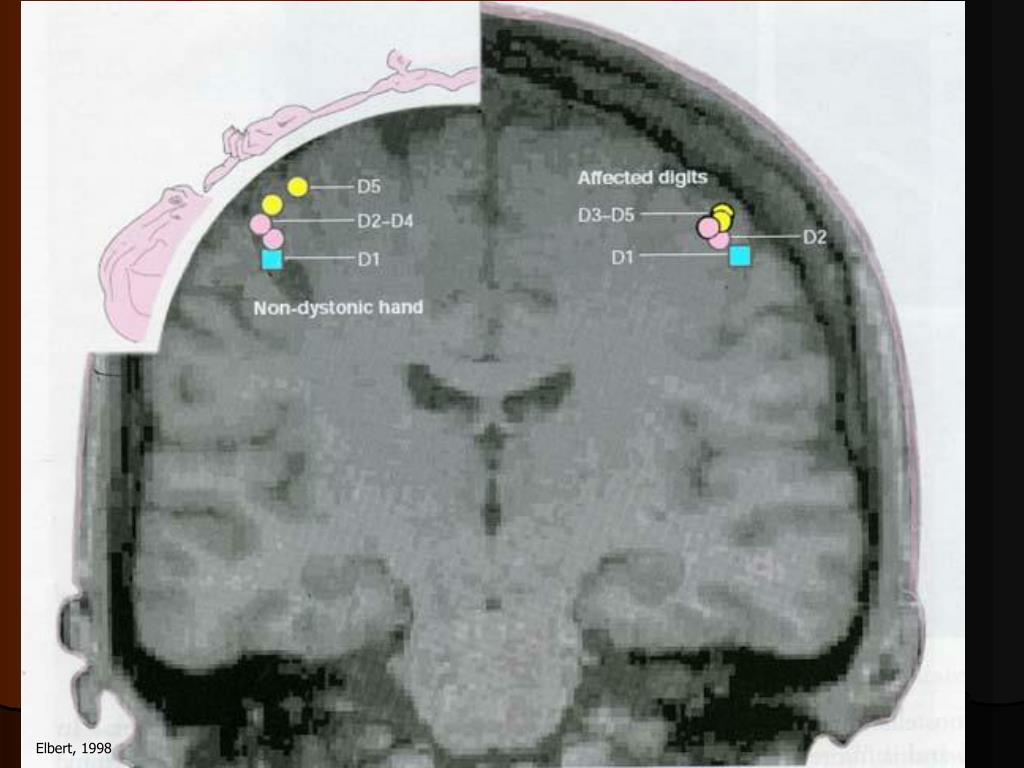

22. Elbert, 1998

23. Afférences dysfonctionnelles Perfectionnisme anxiété Gestes répétitifs Répertoire, style de musique Niveau d’exigence Contraintes sensori-motrices spatiales latéralité Prédispositions Sexe masculin Facteurs héréditaires